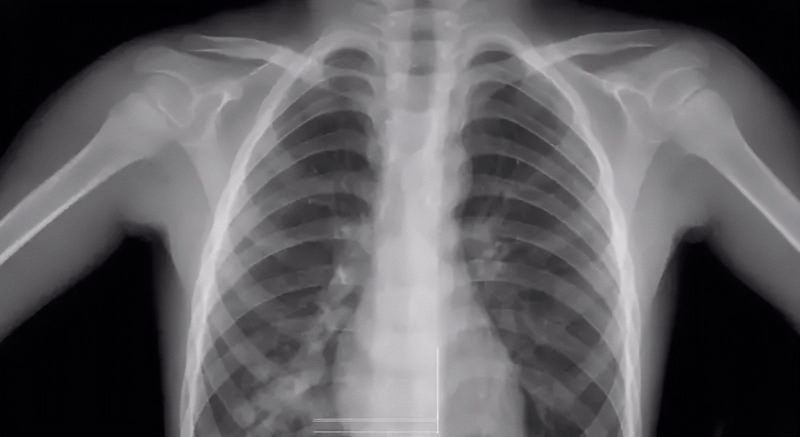

胸透主要检查什么

胸透是一种很常见的x射线检查方法,在医学临床上也会经常用来检查与肺部有关的疾病。但也不是所有的肺部疾病都需要做胸透,毕竟胸透的危害还是有的。此外,若软组织、心脏如果出现异常,通过胸透也能看出一二来,比如胸腔积液、心脏形态的异常等。

胸透的检查方式是利用X射线的穿透性、荧光性和摄影效应等特性,使患者的肺部等在荧屏上形成影像。由于人体组织有密度和厚度的差别,所以当X射线穿透人体时,X线被不同程度的吸收了,到达荧屏上的X射线量就有差异,然后形成黑白对比明显的成像,为医生的诊断提供依据。

胸透检查可以查出是否患有肺结核